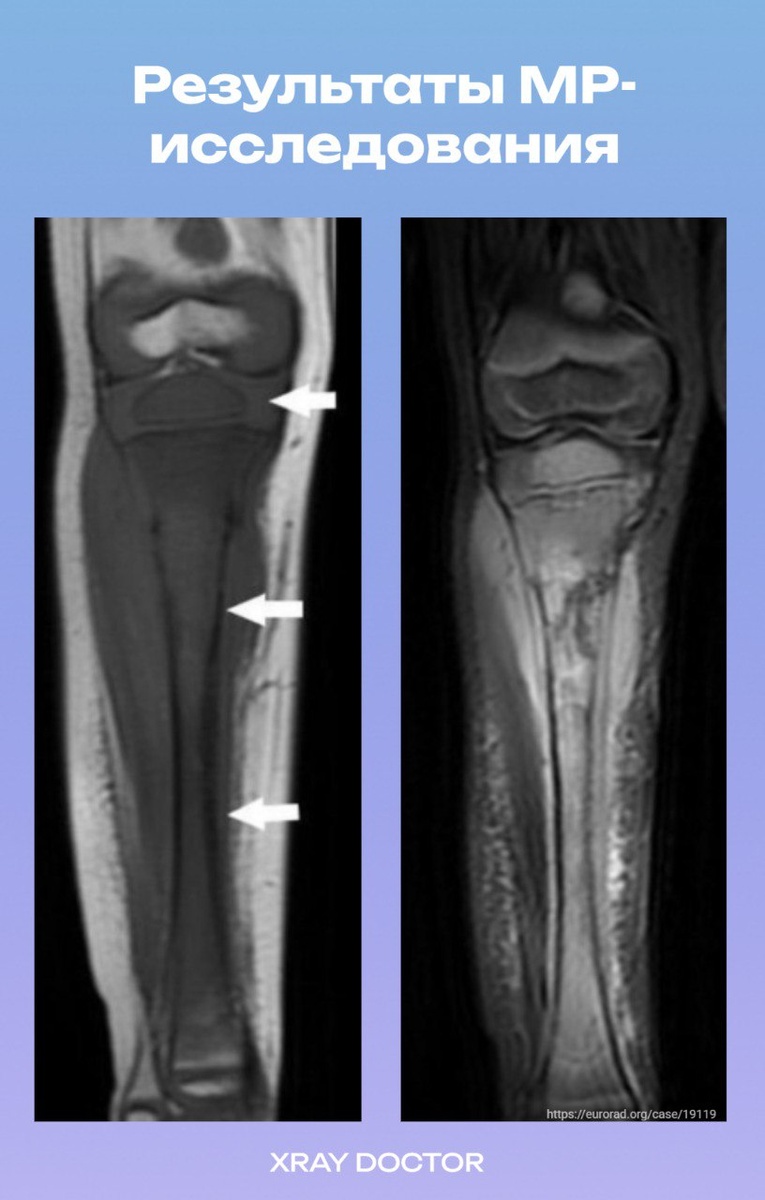

✅Магнитно-резонансная томография (МРТ) подтвердила обширную замену костного мозга в проксимальном отделе большеберцовой кости с прилегающими мягкими тканями, демонстрирующими неоднородное контрастное усиление, кортикальную проницаемость, разрушение кости с очаговым прорывом кортикального слоя. На Т1-взвешенных изображениях (ВИ) костный мозг был гипоинтенсивным, а на STIR- и PD-изображениях с подавлением сигнала от жира — неоднородно гиперинтенсивным.